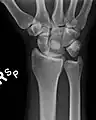

Perilunar dislocation as seen on x-ray.

The lunate bone is the most frequently dislocated carpal bone.